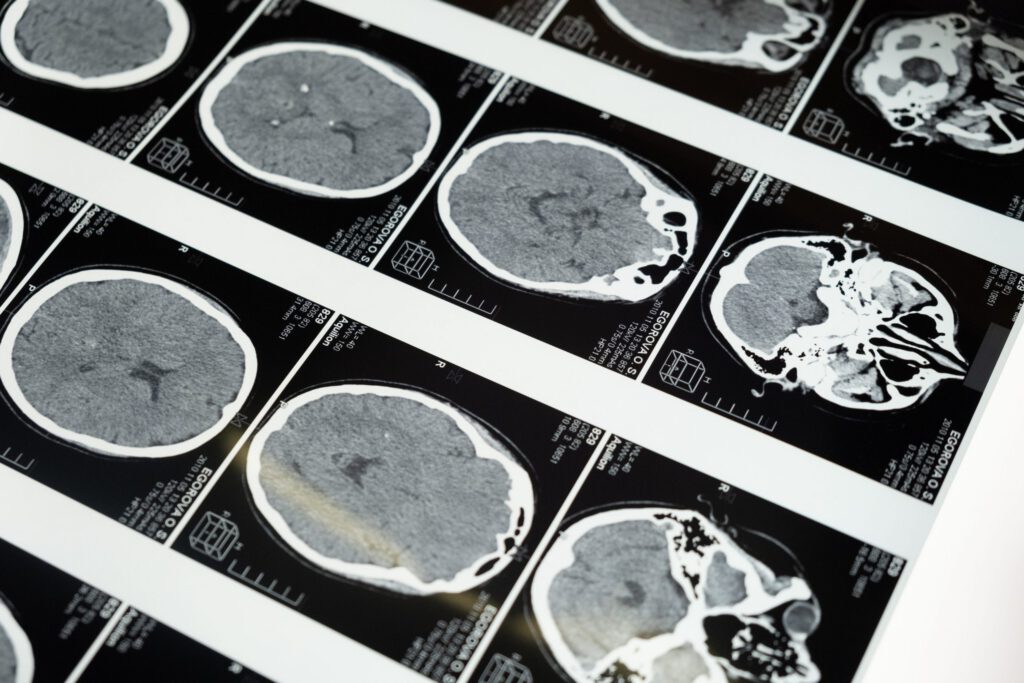

Yn ystod y llawdriniaeth, sy’n cymryd rhwng 12 a 14 awr i’w chwblhau, cynllunnir llwybr yn ofalus i’r ymennydd gan ddefnyddio sganiwr MRI.

Rhoddir y claf o dan anesthetig cyffredinol a, thra ei fod yn dal i fod y tu mewn i’r sganiwr MRI, mae llawfeddygon yn creu agoriadau bach yn y benglog ac yn edafu cathetrau mân i’r ardaloedd targed.

Yna caiff y therapi genynnau ei drwytho ar gyflymder rheoledig trwy ddanfoniad wedi’i wella gan ddarfudiad i ddosbarthu’r therapi trwy’r meinwe. Ar ôl llawdriniaeth, caiff cleifion eu monitro’n agos yn yr ysbyty ac yna’n dychwelyd am ymweliadau dilynol a sganiau.